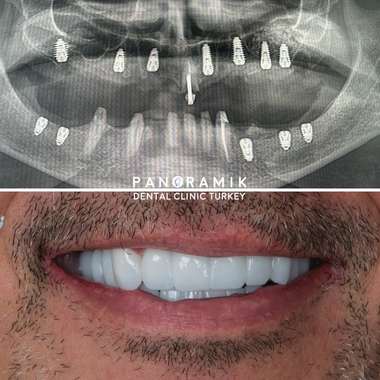

Zahnimplantate sind künstliche Zahnwurzeln, die eingesetzt werden, wenn Zähne fehlen. Sie dienen als Grundlage für den künstlichen Ersatz verlorener Zähne. Viele Menschen mit fehlenden Zähnen leiden unter funktionellen und ästhetischen Problemen. Implantate sind besonders hilfreich, wenn die letzten Zähne im Kiefer fehlen und eine festsitzende Prothese, wie eine Krone oder Brücke, nicht möglich ist.

Bei der Verwendung von Implantaten wird zunächst der zu behandelnde Bereich mit örtlicher Betäubung gemacht. Die Implantate werden anstelle des fehlenden Zahnes eingesetzt. Wird das Implantat anstelle eines zuvor gezogenen Zahnes eingesetzt, entsteht zusätzlicher Platz für das Implantat. Durch das Durchschneiden des Zahnfleisches wird ein kleines Loch geöffnet. Da diese Operation unter Narkose durchgeführt wird, sind keine Schmerzen zu spüren. Es dauert 4-6 Monate, bis das Implantat im Knochengewebe verwurzelt ist. Dieser Vorgang wird als Osseointegration bezeichnet. Mit implantierten Zähnen kann der Patient seinen bisherigen Komfort hinsichtlich Funktionalität und Ästhetik im Alltag wiedererlangen.